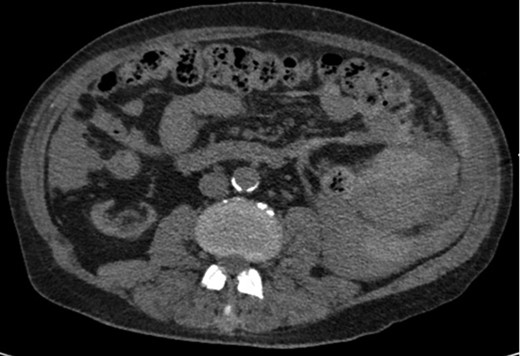

A 68-year-old male with history of living donor renal transplant presented to the ED with acute onset of profound weakness, fatigue, left upper quadrant abdominal pain, hypotension and lactic acidosis. On exam, he exhibited mild left upper quadrant and epigastric tenderness without evidence of peritonitis. CT imaging demonstrated splenomegaly with a large splenic hematoma measuring 15.7 × 9.2 × 12 cm and associated hemoperitoneum (Figs 1–3). In addition, innumerable osseous lytic lesions were identified. Given these findings, emergent surgical consultation was obtained and his coagulopathy reversed. He remained hypotensive despite resuscitation, thus was taken for laparotomy. Upon abdominal entry, a large amount of old clot was evacuated. The abdomen was packed in all quadrants in the standard fashion. Upon removal of the left upper quadrant packs, active hemorrhage began to well from the region of the spleen which was mobilized and removed via splenectomy. Upon gross inspection, the spleen was hyperemic and abnormally indurated, with an avulsion type injury extending several centimeters across the inferior pole. There was no evidence of pseudoaneurysm or other gross pathology. Given the patient was mildly hypothermic and coagulopathic with continued oozing from the retroperitoneum, the decision was made to pack the splenic fossa and place a temporary wound vac. The patient was transported to the ICU for resuscitation and brought back to the OR the next morning for re-exploration and closure. Despite hemodynamic stabilization, he underwent a prolonged hospitalization complicated by atrial fibrillation, renal allograft failure, VAP, and ultimately PEA arrest progressing to asystole. He died 6 weeks following splenectomy. The pathology from the spleen revealed splenomegaly with parenchyma that was replaced with amorphous and acellular eosinophilic material. Histologic staining (Thioflavin-T) was positive for amyloidosis, AL-type. Oncology was consulted based on these findings with concern for lymphoproliferative disorder given osseous findings on CT, splenic pathology, and history of immunosuppression. Bone marrow biopsy was subsequently obtained which showed more than 50% atypical plasma cells/plasma blasts (CD138+; PAX5 negative; EBV (EBER) negative) and no amyloidosis, consistent with multiple myeloma. Urine showed Bence-Jones protein. Serum immunofixation studies were remarkable for a monoclonal IgG lambda gammopathy, consistent with the diagnosis of AL amyloidosis associated with systemic myeloma.

Coronal CT imaging demonstrating splenomegaly with splenic capsule rupture at the inferior pole with heterogeneous fluid in the paracolic gutters and perisplenic region suggestive of hemoperitoneum.